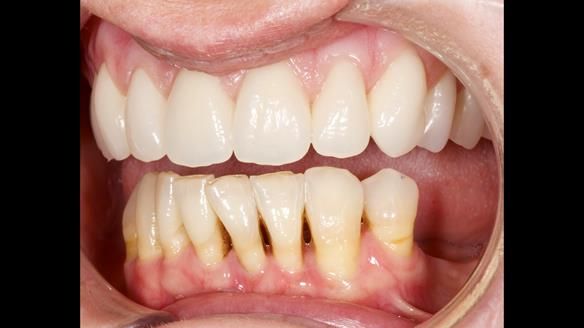

She had previously suffered from generalised periodontitis – stage IV, grade C, currently stable, with reduced attachment across the upper arch.

By the time she came to me, her periodontal condition was stable — but the aesthetics in the upper jaw were very poor.

We provided her with an immediate upper denture (Mk 1), followed by a definitive metal-based upper denture (Mk 2). A lower removable partial denture was discussed, to be made only if needed once the upper treatment was complete. However, at review, this wasn’t necessary — Adnana had excellent neuromuscular control and function, even with a shortened dental arch (SDA).

Rowan, Sam Hesketh and Chris Hesketh provided the stunning technical work. I am very lucky to have them.